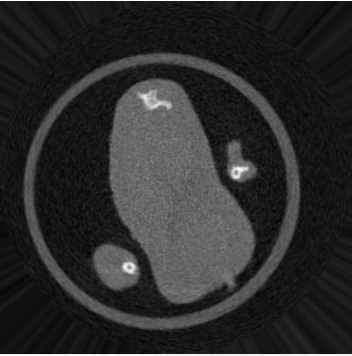

结果贴上

转化成极坐标系

极坐标系转化为直角系

可以看到经过转化,内切圆内区域并没有发生什么变化,内切圆外区域又没什么用(差别是因为两次转化造成的),证明这个计算过程是可行的。代码水平一般将就看吧。